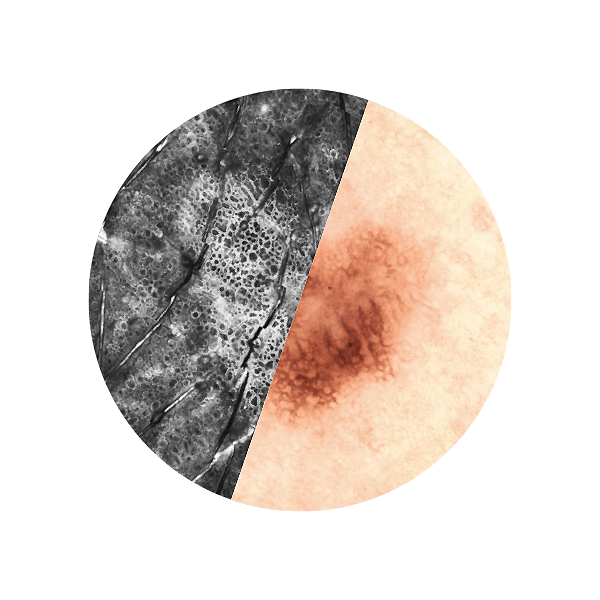

Basal cell carcinoma; imaged with the VivaScope 2500 (left) and after H&E staining (right)

All images courtesy of Prof. Dr Elke Sattler, Dr Martina Ulrich, Prof. Dr Julia Welzel